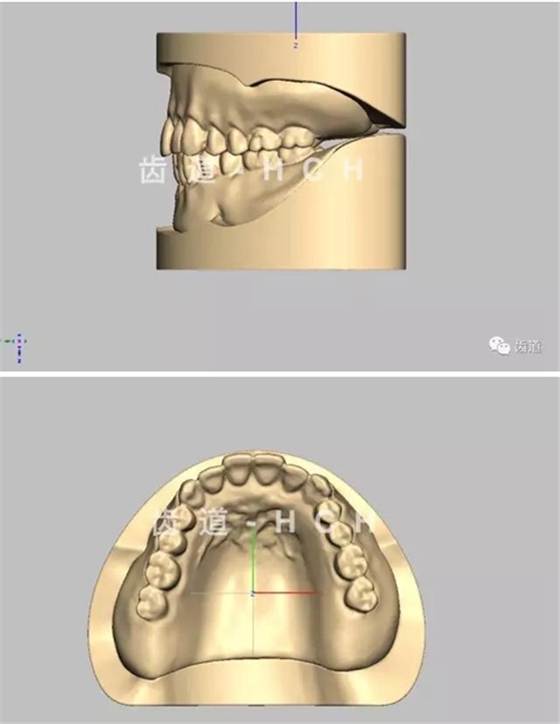

標(biāo)準(zhǔn)全口義齒模型截圖 科貿(mào)嘉友收錄